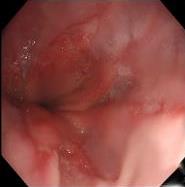

• 结直肠腺瘤住院患者胃镜检查的临床资料分析(附1 052例报告)

2026, 32(1):26-34. DOI: 10.12235/E20250190

摘要 (73) HTML (77) PDF 1.93 M (83) 评论 (0) 收藏

摘要:目的 分析1 052例结直肠腺瘤住院患者行胃镜检查的资料,以期为结直肠腺瘤患者上消化道黏膜病变的早期发现和治疗提供参考依据。方法 回顾性分析2023年1月1日-2023年12月31日在九江学院附属医院消化内科住院的1 052例结直肠腺瘤患者的临床资料,分析患者临床表现、结肠镜结果、胃镜结果和疾病类型分布。结果 1 052例患者均伴随消化不良、胃肠道功能异常、胃食管反流和消化道出血症状,均检查出上消化道黏膜疾病,检出率为100.00%,192例(18.25%)患者只有1个胃镜诊断结果,860例(81.75%)患者有2个或2个以上诊断结果。共检出1 881处病变,以胃黏膜病变为主,其次为食管黏膜病变和十二指肠黏膜病变。前三检出疾病分别为:慢性非萎缩性胃炎932处,胃黏膜糜烂和/或胃肠上皮化生344处,以及胃息肉219处。不同性别疾病类型分布特点:大部分男性食管黏膜病变、胃黏膜病变和十二指肠黏膜病变占比高于女性,男性食管炎占比高于女性;不同年龄段疾病类型分布特点:年龄 > 45岁的患者胃息肉增多;Kaplan-Meier生存曲线显示,与未行胃镜检查的结直肠腺瘤患者相比,行胃镜检查的结直肠腺瘤患者无复发时间更长(HR^ = 13.103,95%CI:6.589~26.057,P < 0.01)。结论 结直肠腺瘤患者建议行胃镜检查,以明确是否存在上消化道黏膜疾病。 > 45岁和男性为高风险人群,建议定期检查,通过早期发现和治疗,预防此类人群上消化道黏膜病变的发生。